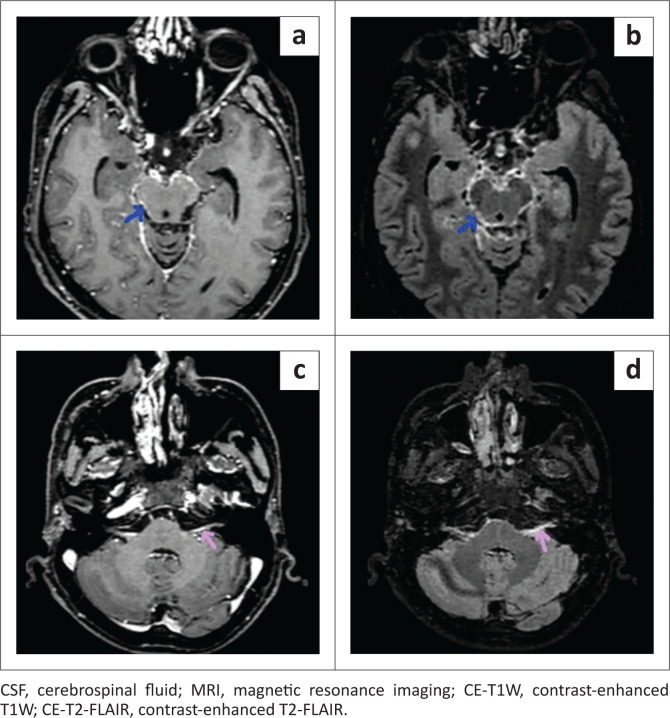

Background: The contrast-enhanced T2-FLAIR (CE-T2-FLAIR) sequence on MRI, through the suppression of CSF and vascular signals, can detect subtle meningeal enhancement in meningitis that may not be appreciable on the routinely used contrast-enhanced T1W (CE-T1W) sequence.

Method: A retrospective study was conducted on 53 patients with clinically suspected meningitis referred for brain MRI. Twenty-seven patients, positive for meningitis on CSF analysis, were classified as the case group; the remaining patients were designated as controls. The pre-contrast, CE-T1W and CE-T2-FLAIR images were assessed and analysed, qualitatively for the detection of abnormal meningeal enhancement, and quantitatively by measuring single pixel signal intensities (SPSI) over the meninges and vessels.

Results: Contrast-enhanced T2-FLAIR demonstrated significantly higher sensitivity (92.59% vs. 57.69%), negative predictive value (92.59% vs. 70.27%) and diagnostic accuracy (94.34% vs. 78.85%) compared to CE-T1W. Additionally, CE-T2-FLAIR showed significantly greater meningeal SPSI and enhancement than CE-T1W.

Conclusion: Contrast-enhanced T2-FLAIR is better at detecting abnormal meningeal enhancement in meningitis than CE-T1W, because of significantly greater signal intensity and enhancement of the meninges compared to vessels.